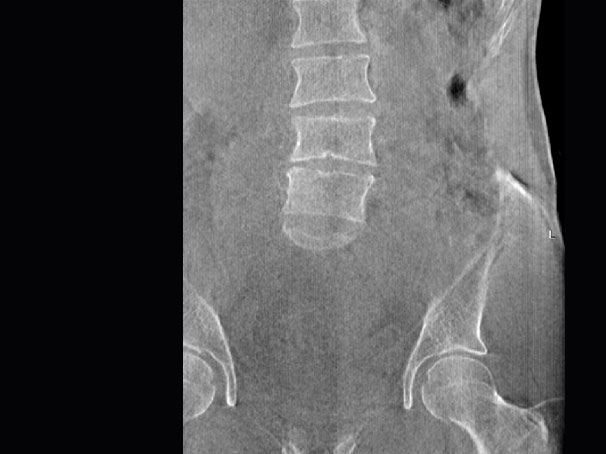

髖關節

腰椎